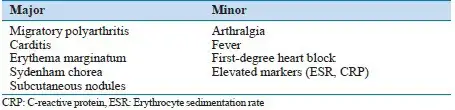

琼斯标准将临床表现分为主要标准和次要标准。主要标准包括:心脏炎、多关节炎、舞蹈病、环形红斑和皮下结节。次要标准包括:发热、关节痛、既往风湿热或风湿性心脏病史、血沉升高或C反应蛋白阳性、心电图PR间期延长。诊断急性风湿热需要存在两个主要标准,或一个主要标准加两个次要标准,加上近期链球菌感染的证据。

琼斯标准的制定是风湿热诊断史上的里程碑。它不仅为临床医生提供了统一的诊断框架,也为流行病学研究和临床试验奠定了基础。然而,随着对风湿热认识的深入和医学技术的发展,琼斯标准也在不断更新。